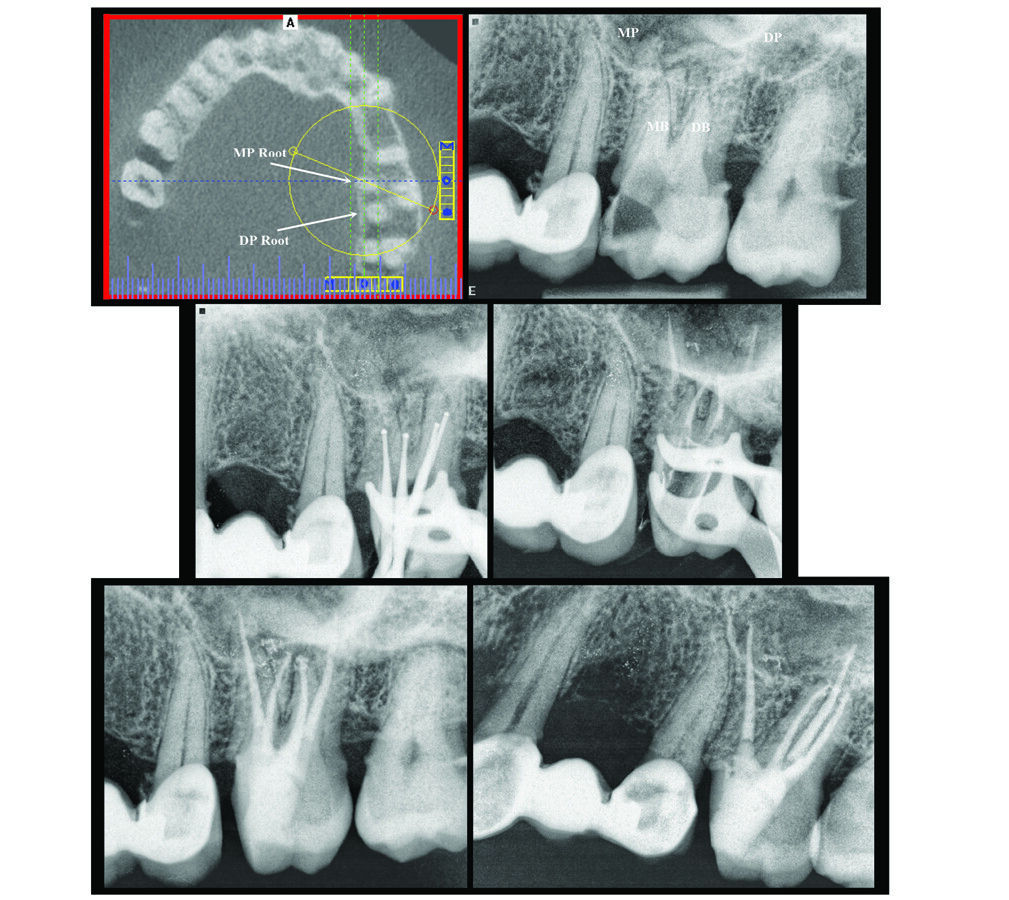

Tooth No. 14: Necrotic pulp with SAP and associated severe coronal breakdown presenting isolation and clamp stabilization challenges that were managed by pre-endodontic bonded build-up. Unusual root morphology made this an interesting case.

Complexities included:

Severe coronal breakdown and associated isolation challenges. Managed by slow-speed #6 round cariesectomy bur. Followed by bonded pre-endodontic reconstruction of the mesial wall.

Severe calcification of all canals. Managed by careful slow-speed round bur troughing to identify canal remnants on the chamber floor. The canals were further excavated by a series of decreasing-diameter deep narrow-shafted tiny slow-speed round troughing burs to a level where files could enter all four canal canals.

Unusual root morphology. Two separate palatal roots and two constricted buccal roots. Clarified by a pre-treatment CBCT scan.

At completion, to facilitate both a robust endodontic coronal seal and a durable build-up — and while still under rubber dam isolation protocol — composite was bonded directly over gutta percha from sub-orifice levels to the cavo-surface of the access cavity.